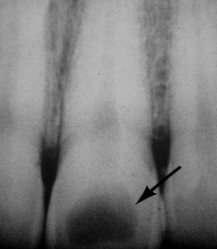

rare, injury to pulpal tissue (trauma)

internal resorption

what is the cause of this lesion

trauma to the pulp